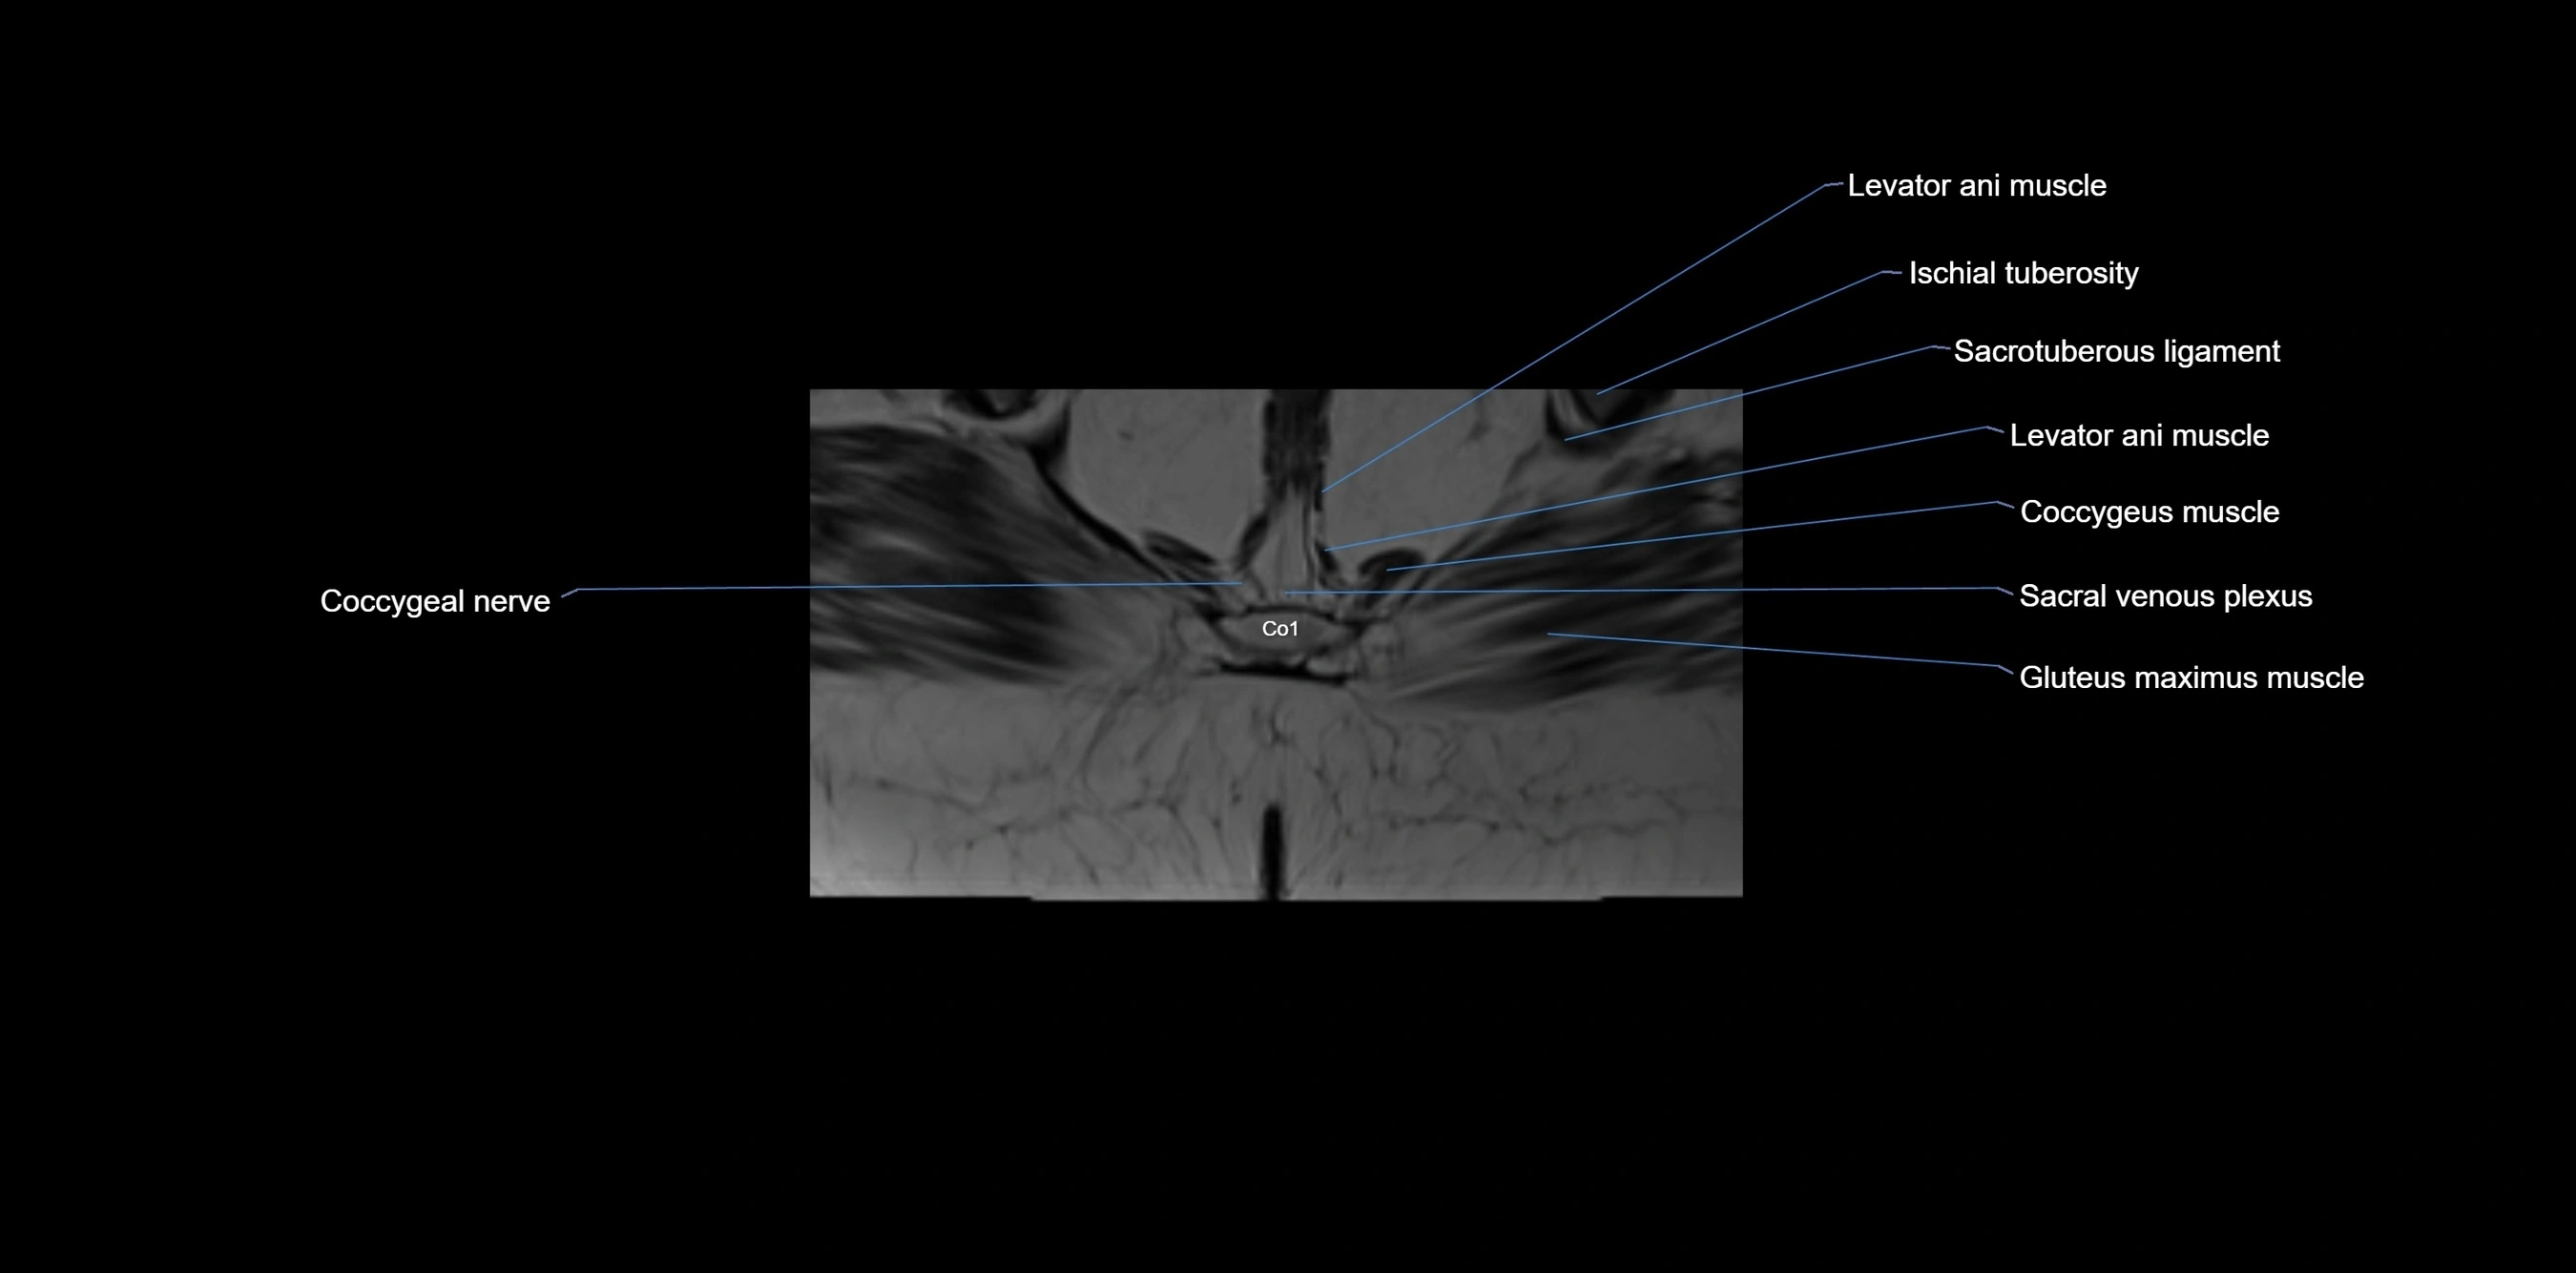

CT image

image